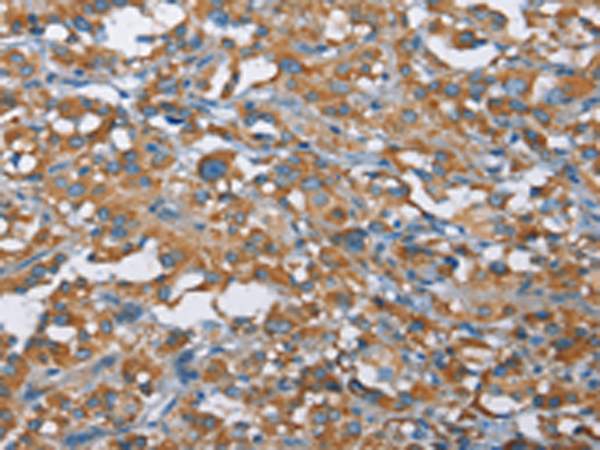

分类: 科研抗体货号: P07391别名: LPS; PIT; PPS; VWS; OFC6; PPS1; VWS1应用: WB,IHC反应种属: Human, Mouse